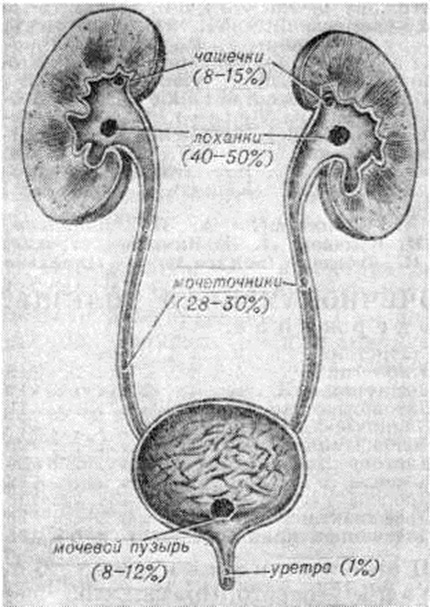

Почечнокаменная болезньПочечнокаменная болезнь (nephrolithiasis; синонимы нефролитиаз) — хроническое заболевание, характеризующееся нарушением обменных процессов в организме и местными изменениями в почках с образованием в их паренхиме, чашечках и лоханках камней, формирующихся из солевых и органических соединений мочи. Почечнокаменная болезнь является основным и наиболее частым проявлением мочекаменной болезни, или уролитиаза (смотри полный свод знаний), заключающейся в наличии мочевых камней в почках, мочевом пузыре и уретре. «Каменная болезнь» известна с глубокой древности, о чем свидетельствуют памятники письменности Древнего Египта, Персии, Китая, Индии и другие Камни мочевого пузыря и почек обнаружены в мумиях с давностью захоронения 3500—4000 лет до нашей эры. Первое описание операции камнесечения принадлежит римскому врачу А. Цельсу (1 век нашей эры). Имеются сведения о лечении Почечнокаменная болезнь в период средневековья. В конце 17 век опубликованы данные о строении мочевых камней и кристаллов мочевых солей. Со второй половины 19 век, благодаря развитию морфологии, топографической анатомии, внедрению лабораторных и рентгенологическое методов исследования, представления о Почечнокаменная болезнь получили научное обоснование. В России первую операцию при Почечнокаменная болезнь произвёл Н. В. Склифосовский в 1883 год Значительный вклад в учение о Почечнокаменная болезнь внесли С. П. Федоров, Р. М. Фронштейн, М. А. Мир-Касимов, Г. С. Гребенщиков, Ранделл (A. Randall), Карр (J. A. Carr), Бойс (W. Н. Воусе) и другие Оглавление Почечнокаменная болезнь у детей СтатистикаПочечнокаменная болезнь встречается во всех районах мира, но распространена она неравномерно. Относительно низкая заболеваемость наблюдается в некоторых районах Севера, Африки и другие Районы с частой заболеваемостью (эндемические очаги) расположены в странах Ближнего Востока, Индии, Китае, Австралии, Латинской Америке и отдельных регионах Европы. В СССР эта болезнь также распространена неравномерно. Так, в районах с холодным и умеренным климатом ежегодная заболеваемость составляет 0,19 — 1,0 и выше на 10 000 жителей, в эндемических районах республик Средней Азии и Кавказа ежегодная заболеваемость колеблется в пределах 2,5—3,6 и более на 10 000 жителей. По данным большинства урологов, Почечнокаменная болезнь составляет 25—35% от всех заболеваний почек хирургического профиля. Заболевание встречается почти с одинаковой частотой у мужчин и женщин. Камни локализуются несколько чаще в правой почке, чем в левой, чаще в лоханке, чем в чашечках, или одновременно в лоханке и чашечках. Частота расположения камней в почках и мочевых путях представлена на рисунке 1. Однако эти данные могут меняться в зависимости от возраста больных, климатогеографической зоны и других причин. По химический составу камни бывают оксалатные — до 40% случаев, фосфатные — в 27—30%, уратные — в 12—15%, цистиновые и белковые — до 1%, смешанного состава— в 20— 30% случаев. Соотношение камней различного химический состава у больных также неодинаково; оно зависит от климатогеографической зоны, условий окружающей среды, содержания солей в питьевой воде и пищевых продуктах, характера питания, возраста. |